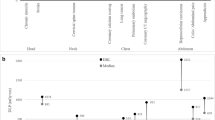

Table 2 summarizes CT radiation dose indices for the participating sites and CT protocols. institution and across different institutions for the same protocols (p < 0.001) (Fig. 3). Table 3 presents data on significantly different total iodine load and iodine delivery rates at different CT protocols across the 43 participating sites (p = 0.001). There was no significant difference between radiation doses for non-contrast (CTDIvol 24 [16–30] mGy; DLP 633 [414–702] mGy·cm) and post-contrast phases (22 [19–27] mGy; 648 [392–694] mGy·cm) (p = 0.142). Most sites with bolus tracking for chest and AP CT had lower CTDIvol than the sites with fixed scan delays (p < 0.001). Regardless of the CT vendor and model, body size, and scan protocols, most CT examinations were performed at 120 kV or 140 kV.

There was no significant correlation between patients’ size (BMI) and ICM or radiation doses for any of the six CT protocols included in our study (r2 ≤ − 0.1 to 0.1). When comparing median DLP and CTDIvol levels between different patient sizes, we noticed no significant difference between radiation doses for underweight-normal and overweight-obese patients (p > 0.05). Furthermore, in terms of total iodine load comparison in terms of different patient sizes, underweight-normal BMI patients received significantly lower total iodine load (p < 0.05) (Fig. 4). Regardless of the CT protocols, exams with bolus tracking and test bolus timing of scan delay had lower radiation doses (CTDIvol) as compared to the fixed scan delay (p < 0.001).

Box and whisker plots illustrate variations in CTDIvol and total iodine volume among patients in different BMI groups for routine head, head CTA, routine chest, PE protocol, routine AP and liver protocols. The bimodal distribution of radiation dose in underweight and obese patients (higher dose for smaller patients) for head CTA and chest CT could be related to a combination of variable and suboptimal acquisition factors